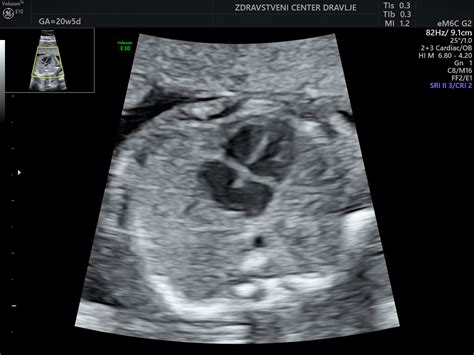

V primeru, ko je zadnja menstruacija nastopila 7. novembra 2013, je bila ženska ob pregledu noseča približno 7 tednov in 6 dni. V tem času bi moral biti plod že dobro razvit, z zaznavnim srčnim utripom. Vendar pa je bil na ultrazvočnem pregledu pri gestacijski vrečki (GV) s premerom 25 mm, kljub vidnemu rumenjakovemu mehurčku, ki naj bi bil že skoraj prevelik, plod in njegov srčni utrip nista bila zaznavna. Ginekolog je izrazil zaskrbljenost, saj bi ob takšni velikosti GV srčni utrip že moral biti viden. Ta situacija lahko nakazuje na nepravilen razvoj nosečnosti, kot je na primer zadržani splav, kjer plod odmre, vendar se ne izloči samodejno, ali pa zgodnji spontani splav. V primeru, da se ugotovi le prazna gestacijska vrečka brez ploda, to lahko kaže na tako imenovani "blighted ovum" ali snetljivo jajce, kjer se jajčece oplodi, vendar se zarodek ne razvije.